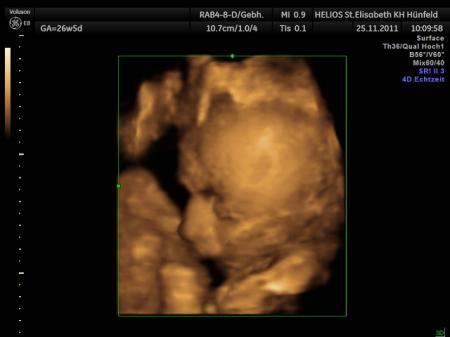

Bild zu

Hallo, meine Kleine hat auch ab und zu Schluckauf. Vor drei Tagen habe ich es wieder mal gespürt, als wir gerade bei Freunden eingeladen waren. Da habe ich zu meinem Mann gesagt: Du, ich glaube sie liegt schon mit dem Kopf nach unten, der Schluckauf ist eindeutig am Unterbauch. Und was soll ich sagen: Gestern beim Screening hat sich gezeigt, dass es stimmt - supi! LG Angela